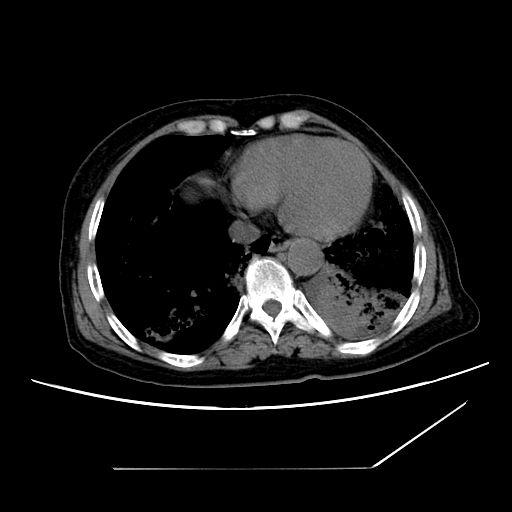

标题: CT25393:病人45岁,咳嗽,吐黄痰带血丝,发热,胸闷月余 [打印本页]

标题: CT25393:病人45岁,咳嗽,吐黄痰带血丝,发热,胸闷月余

1、左肺中央型肺癌并双肺弥漫性转移   2、双肺部感染    3、肺大泡     4、左侧胸腔积液

双侧肺弥漫性病变,可见“空泡征”及“蜂窝征”,考虑肺泡癌可能性大,左侧胸腔积液,考虑胸膜受累可能!

1)不排除肺泡癌可能。2)左侧胸腔积液。